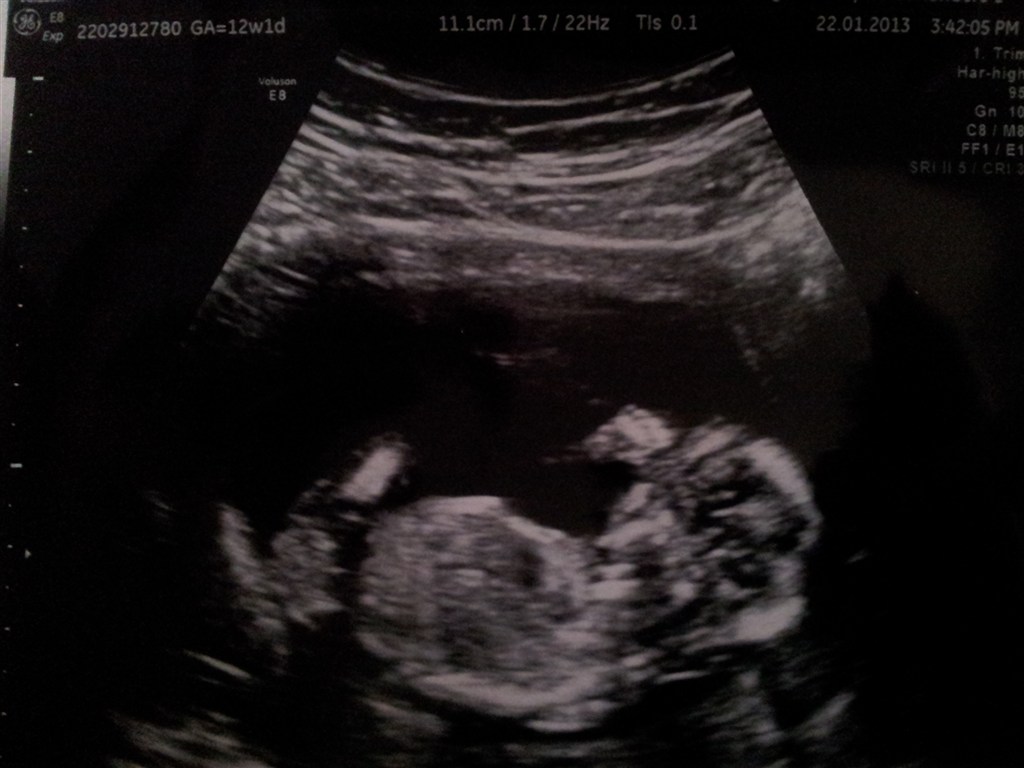

SÅ har jeg været til NF-scanning! Det gik bare helt fantastisk, og vi fik en lav risikovurdering for Downs

Den lille var rigtig livlig og vi fik både hørt hjertelyd, set urinveje, mavesæk, nyrer etc. Det hele var bare top i orden. Det var virkelig en STOR og fantastisk oplevelse!

Jeg blev sat en uge frem, så terminen hedder nu den 28. juli 2013.

På billedet er vores lille guldklump, hvor man også lige kan se dens lille hånd oppe til højre